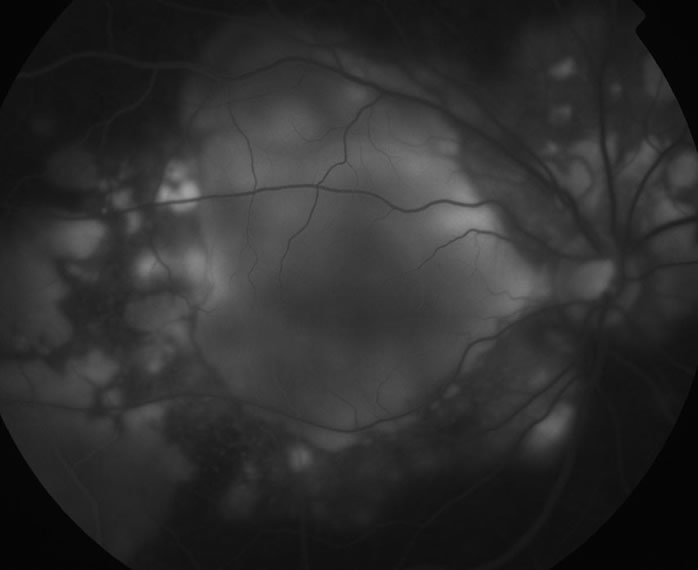

IA後期像

急性期の原田病症例におけるIA後期像。散在する斑状低蛍光がみられる。

出典

img

1: 著者提供